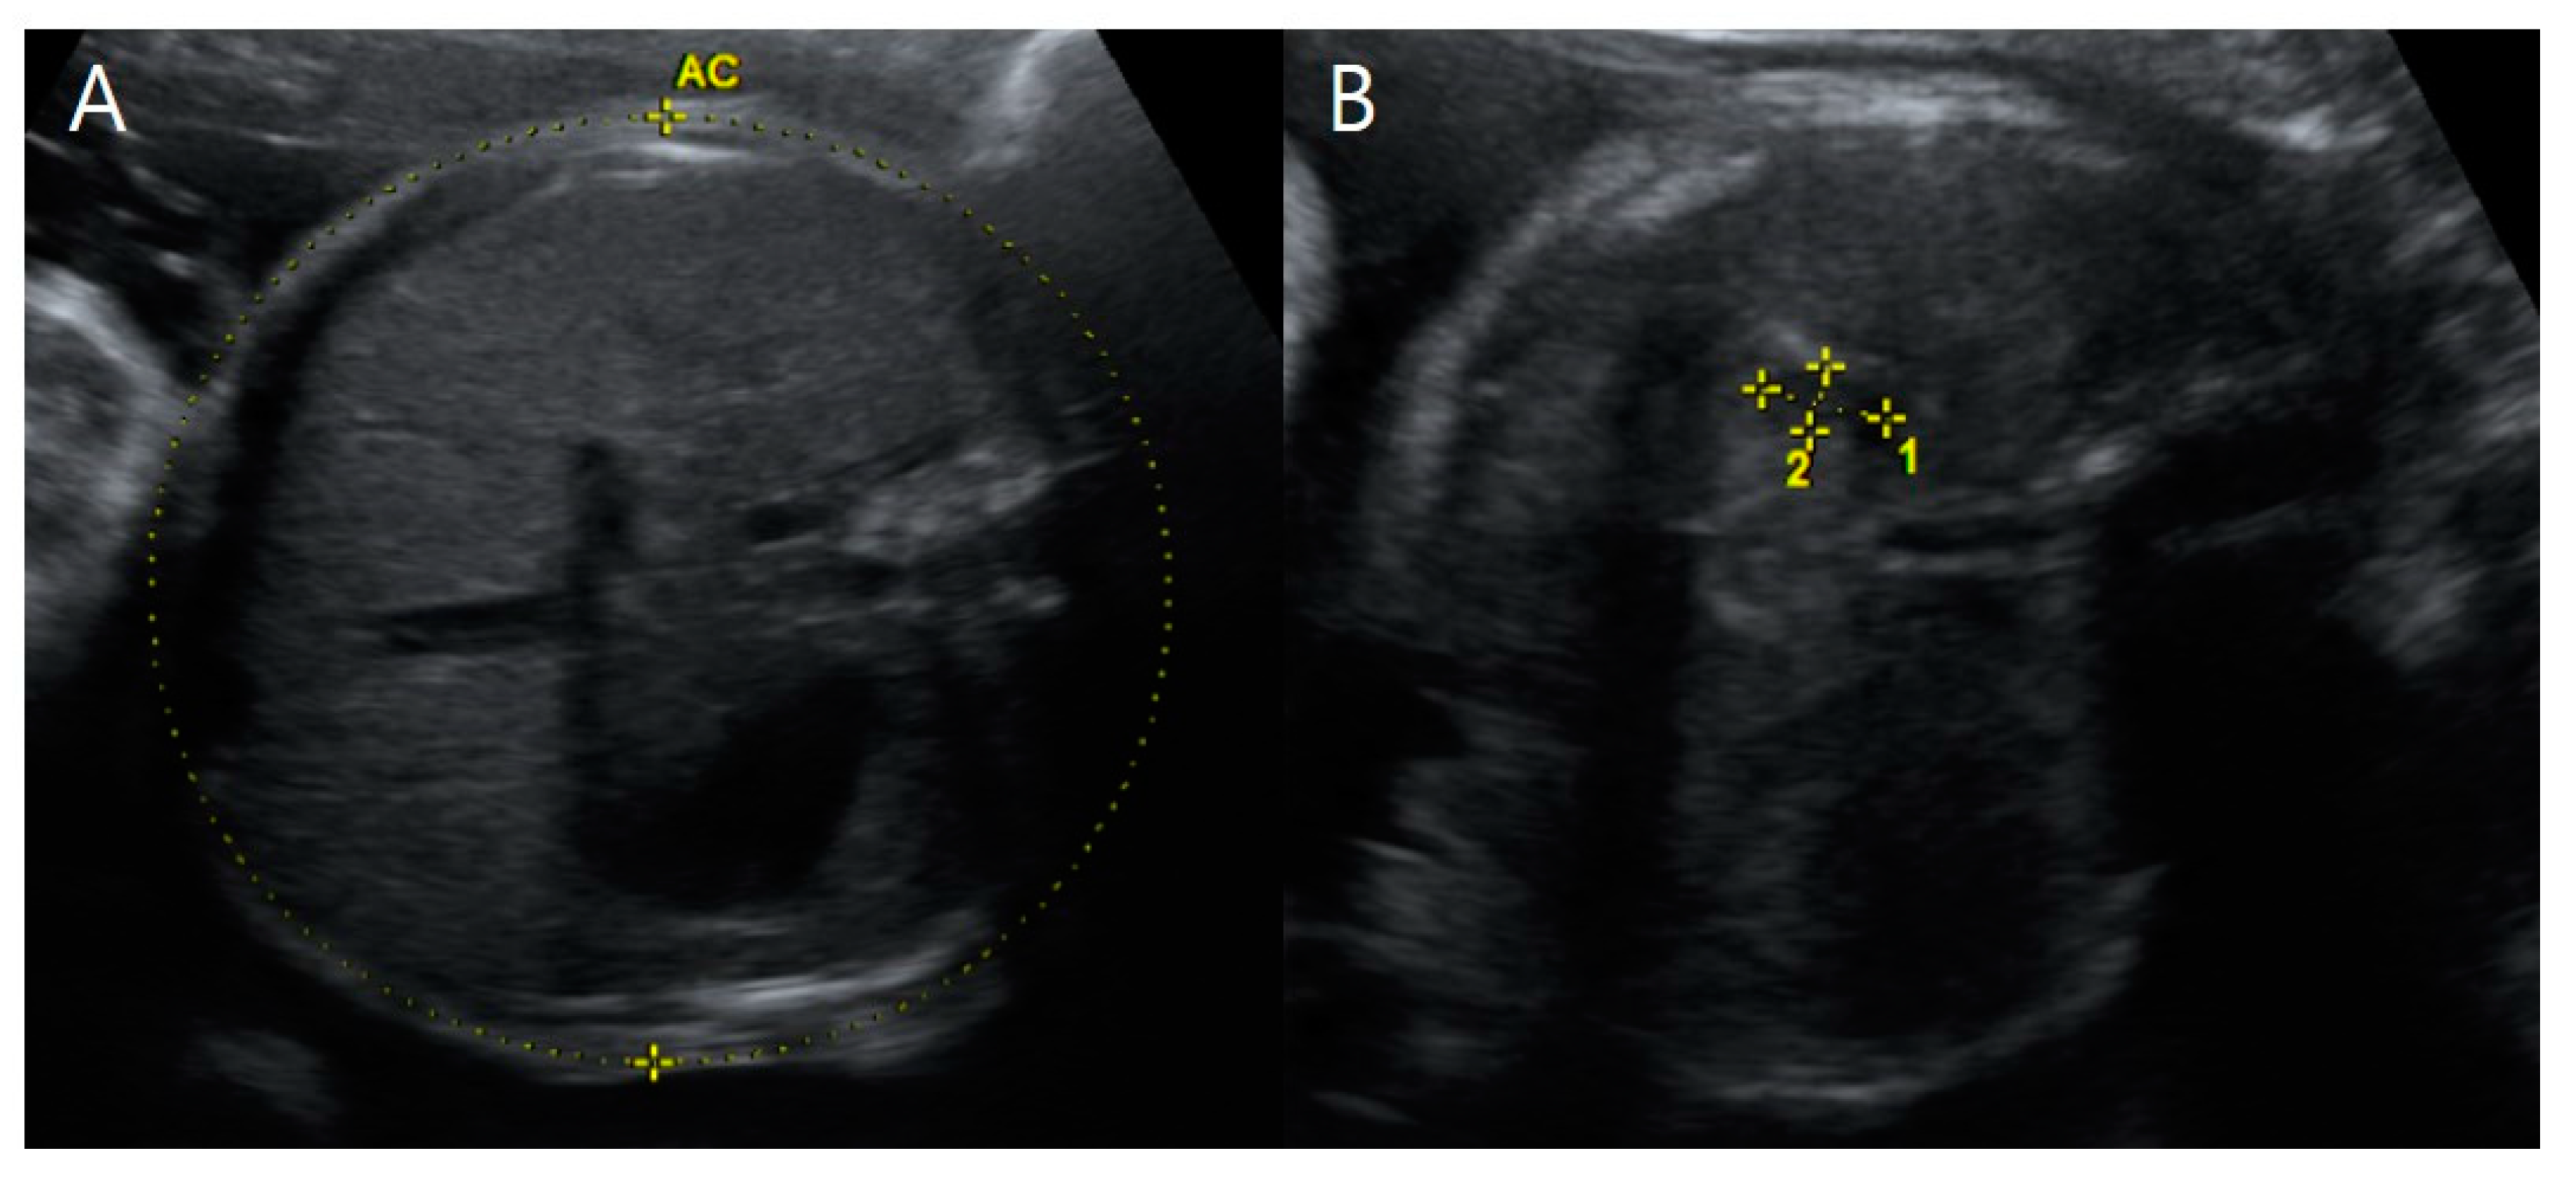

On the transverse view, we noted a small stomach in association with polyhydramnios in fetus A. These were crucial findings from the prenatal ultrasound examinations for the diagnosis of tracheoesophageal fistula (TEF), which were confirmed by 3D CT (Figure 6 and Figure 8). Compared with the normal-sized stomach filled with amniotic fluid in fetus B, fetus A’s stomach size did not increase over time, as shown by repeated exams (Figure 6).

Figure 6. Transverse view of prenatal ultrasonography at 31 + 1 weeks gestation. (A) Fetus B, a healthy female with a normal stomach filled with amniotic fluid. (B) Fetus A, an affected male with a small stomach sized 0.91 × 0.47 cm2 accompanied by polyhydramnios and without time variance, highly suggesting tracheoesophageal fistula. Note that the abnormally increased amniotic fluid is not shown in this figure.